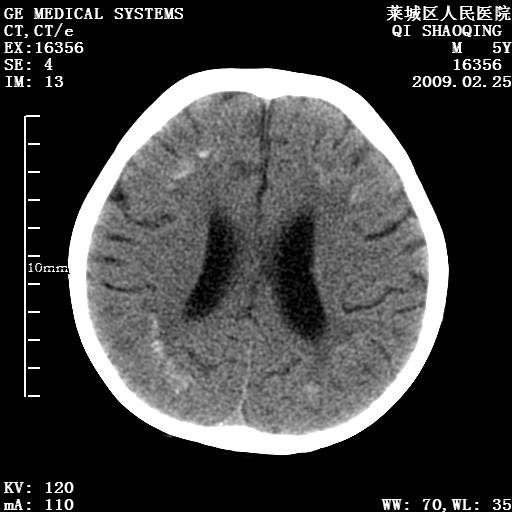

以下是引用wangzhengyuan在2009-2-28 10:22:00的发言:[br]甲状旁腺功能减退引起的脑改变.

以下是引用zsl6918在2009-2-28 10:17:00的发言:[br]首先考虑甲状旁腺功能低下所致,可结合实验室检查明确.另外需除外先天性宫内感染所致.

以下是引用余辉在2009-3-1 9:35:00的发言:[br]患者明显的肢体及智力改变,不支持fahr病,多考虑甲旁低,有可能伴有甲低(呆小症).进一步检查。